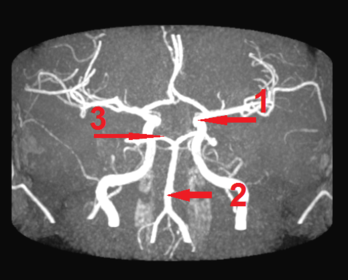

1) identify the picture 2) identify 1,2,3 1) circle of willis 2) 1- internal carotid artery 2- basilar artery 3- posterior cerebral artery